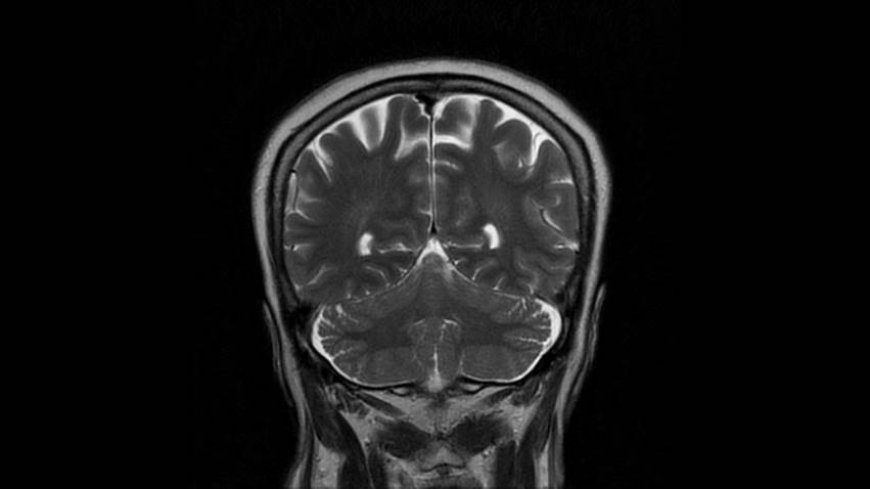

MRI of Brain

Coronal T2